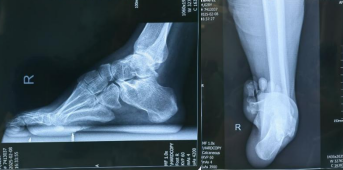

术前X线